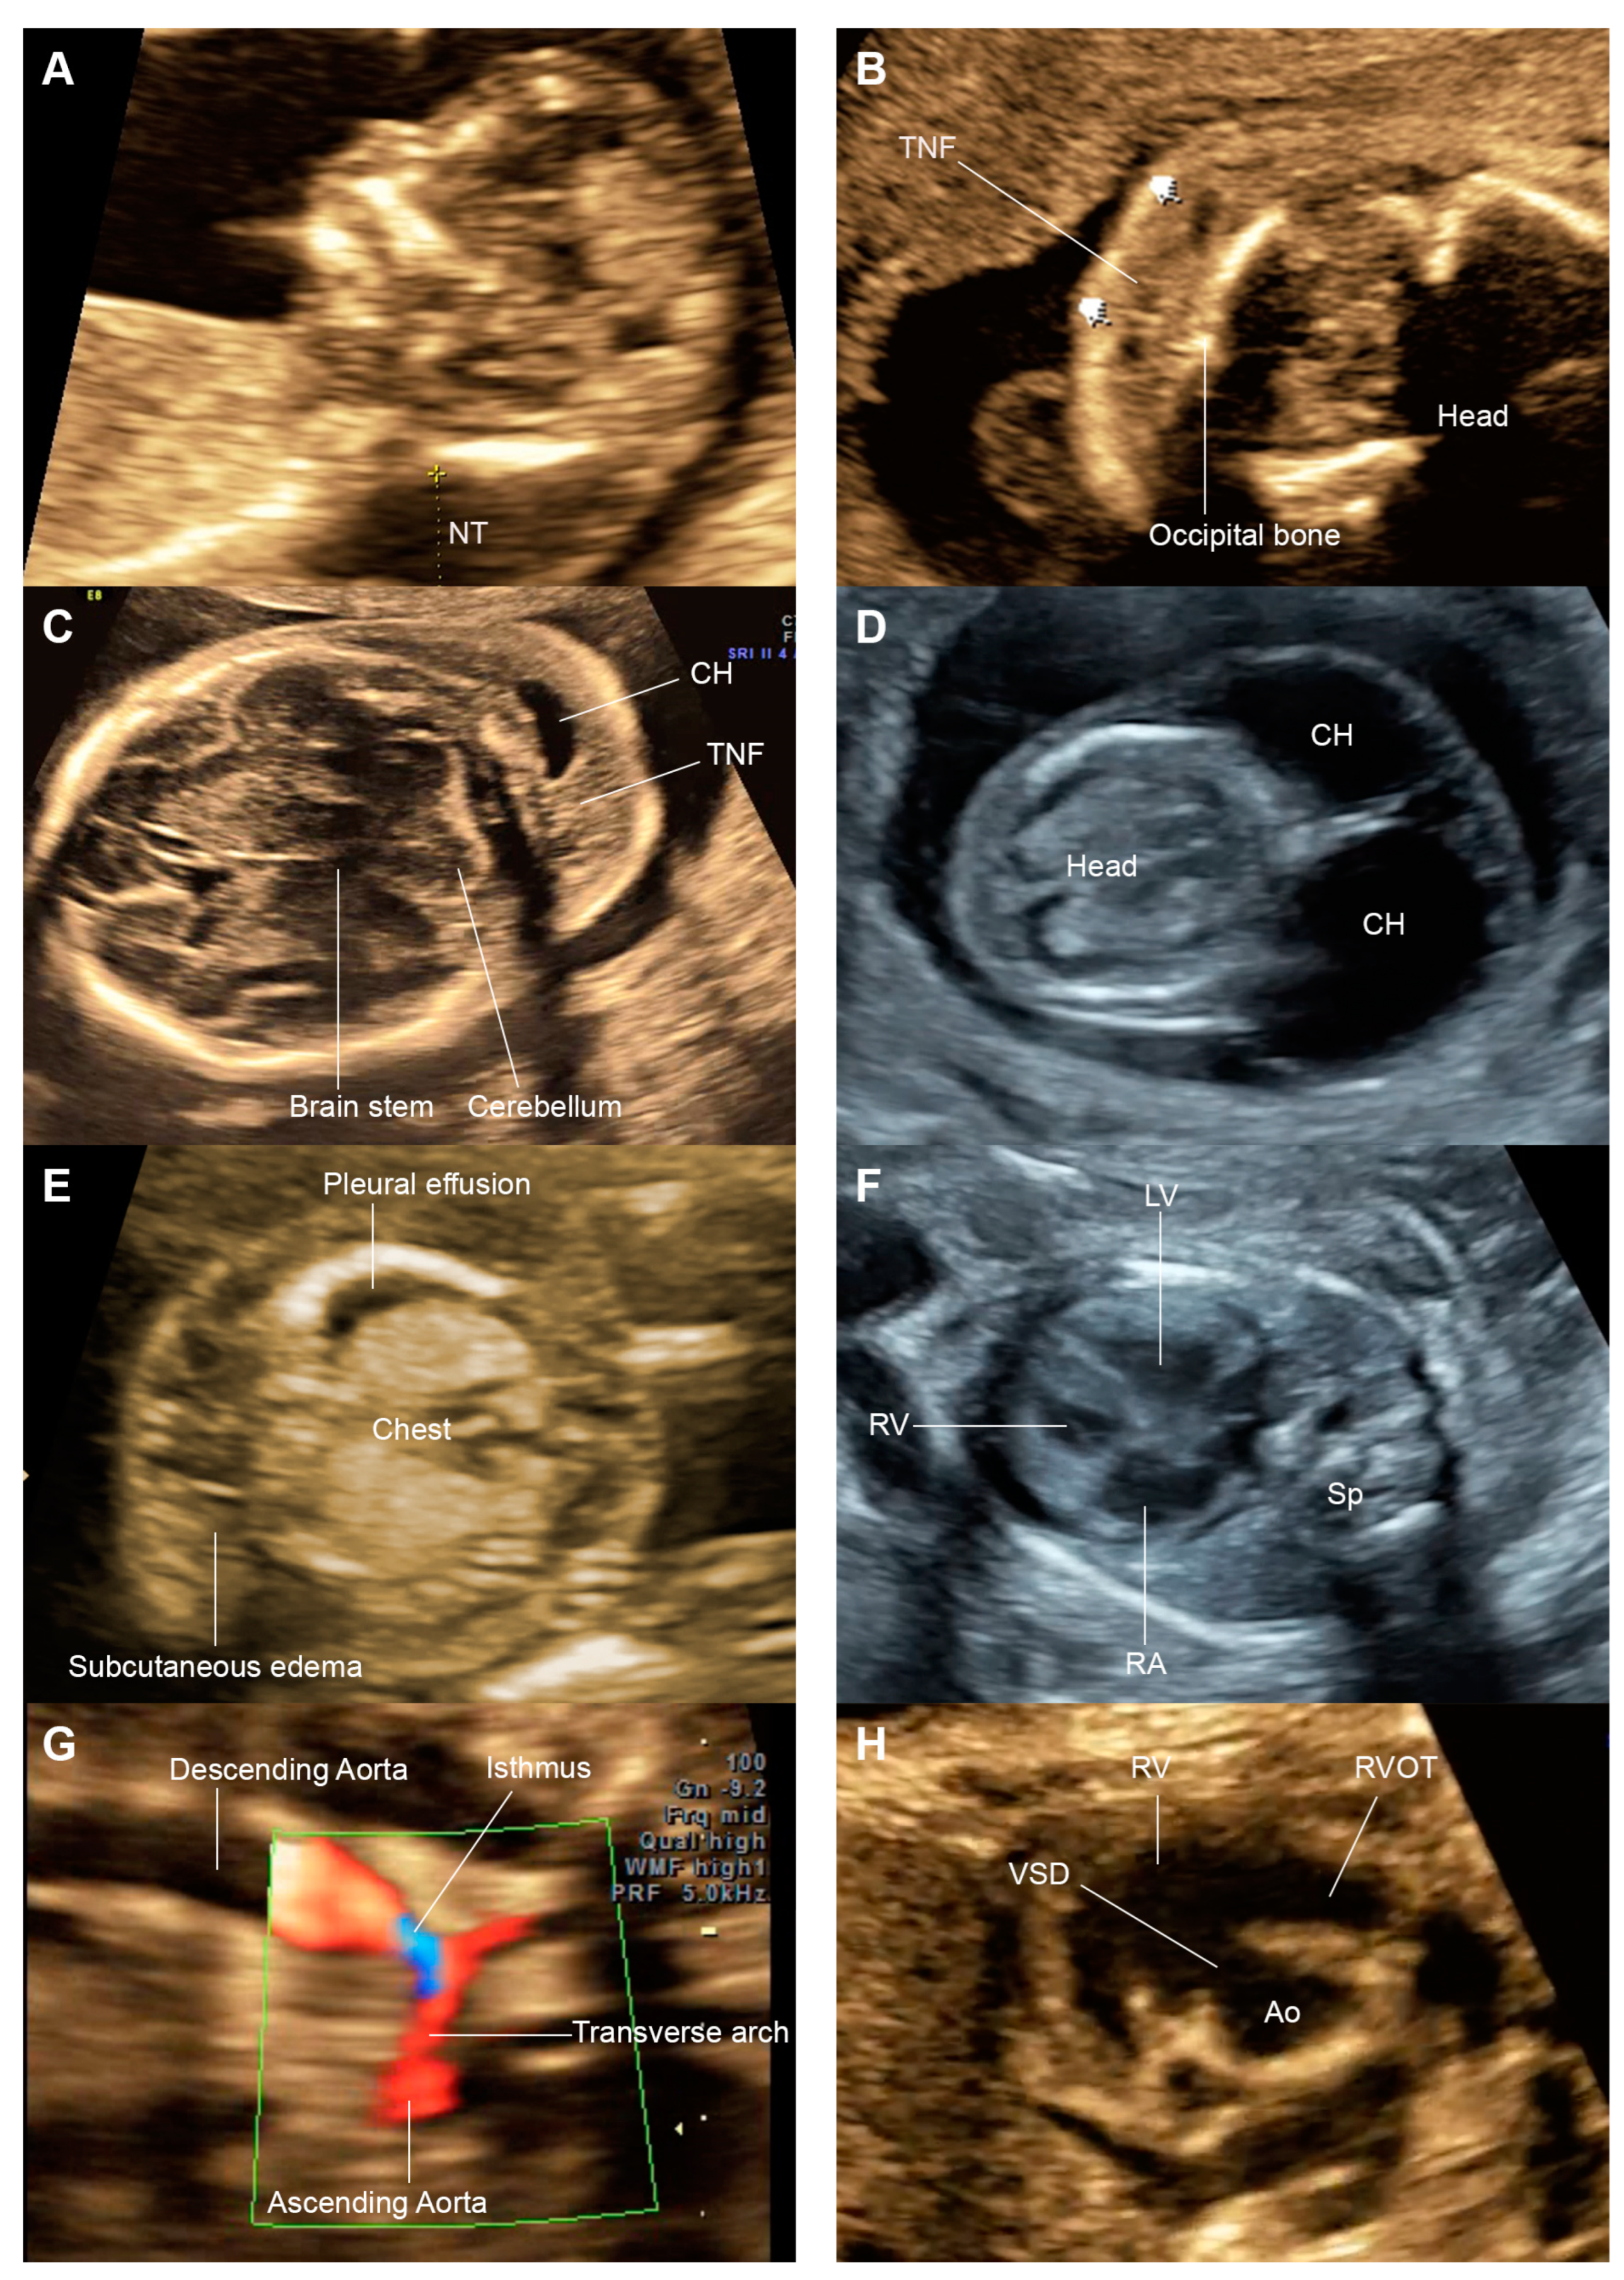

| 1 | 13,20 | y | y | y | HCM, ostium primum ASD, CoA | y | y | y | y | y | y | n | n | n | y | y | Duplex kidney | PTPN11 | Features of NS, delivery at 30 wk, female, 1750 g, death at day 21 |

| 4 | 13,17, 24 | y | y | y | HCM, Right- sided AoA | y | y | y | y | n | y | n | y | n | n | n | Portosystemicshunt Posteriorly rotated ear | RIT1 | Features of NS, delivery at 35 wk, female, 3130 g, death at 1 month |

| 5 | 13,17, 21 | y | y | y | VSD, Left SVC, HCM | n | n | n | n | y | n | n | n | n | n | n | LZTR1 | Features of NS, term delivery at 40 wk, 3215 g, survive | |

- Lymphatic drainage disorders (in both the first trimester and second/third trimesters)The most consistent finding in the first trimester was thickened nuchal translucency, accounting for 71.4% of cases, followed by cystic hygroma (16.3%). The most common consistent findings in the second/third trimesters was fluid collection in at least one body space, accounting for 59.3% of cases (including hydrops fetalis; 46.2%), followed by cystic hygroma (33.0%), and thickened nuchal fold (26.4%).

- Cardiac abnormalities (in the second/third trimesters)Relatively specific abnormalities included ventricular hypertrophy (33.7%) and pulmonary stenosis (13%), and other non-specific disorders included VSD (12%) and small left heart side (9.8%). Note that ventricular hypertrophy exhibited a wide range of severities, ranging from localized to diffused hypertrophy and eventually HCM.